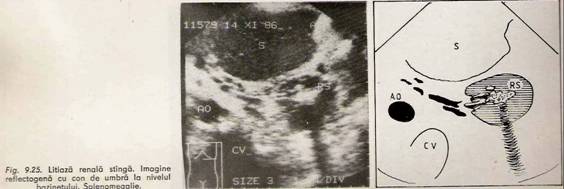

Calculul, indiferent de caracterul radiologic, apare sub forma unui arc ecogen cu con de umbra situat decliv, mobilizabil odata cu miscarea bolnavului.